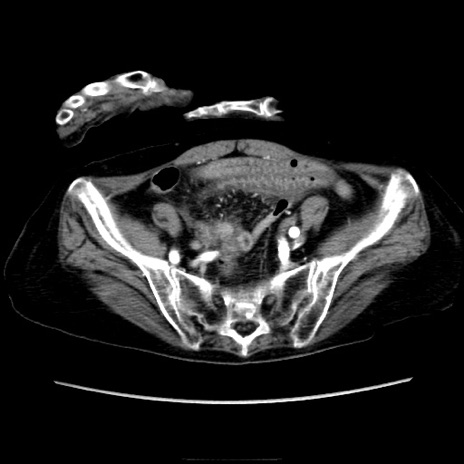

症例40(横断像)

【症例】90歳代女性

【主訴】腹痛・嘔吐

【現病歴】 食欲低下、嘔吐があり昨日他院受診。肺炎と診断され入院となる。入院後より腹部全体に圧痛あり。胃管留置され経過みていたが、症状持続するため、

当院転院となる。

【既往歴】胸椎圧迫骨折、胆石症

【身体所見】腹部:中央に激痛あり、圧痛あり、反跳痛不明

【データ】WBC 17100、CRP 18.82

横断像